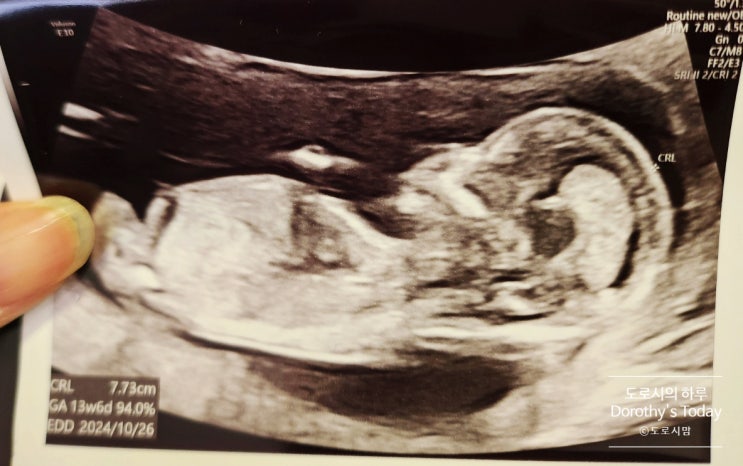

[임신기록] 임신12주차 / 1차 기형아 검사

2024. 04. 26 (금) 임신 12주차 1차 기형아 검사, 첫 입체 초음파 이맘 때쯤 예비맘들의 가장 큰 관심사 바...